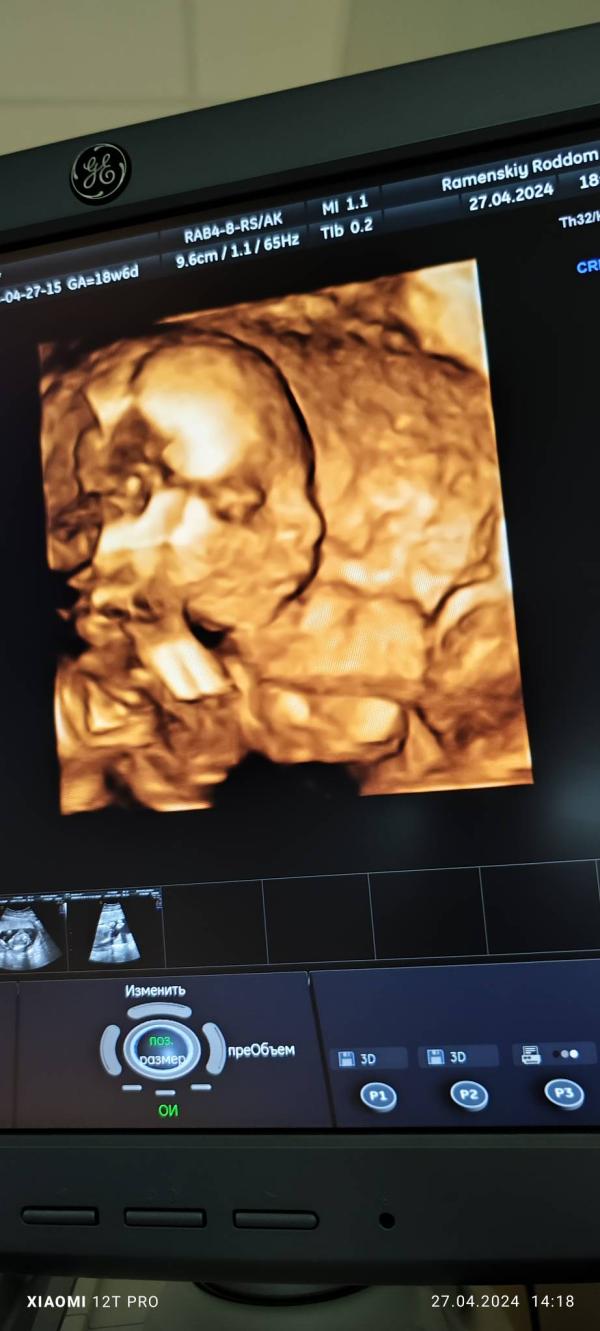

По УЗИ мы уже перегоняем на неделю)

267 грамм сладкого милого пупса💖

@moms_nail ну там видимо не только по весу, но малыш у меня ещё с доскрининговых УЗИ был постарше, чем по месячным. И на первом скрининге был на 3 дня старше) а сейчас вот)